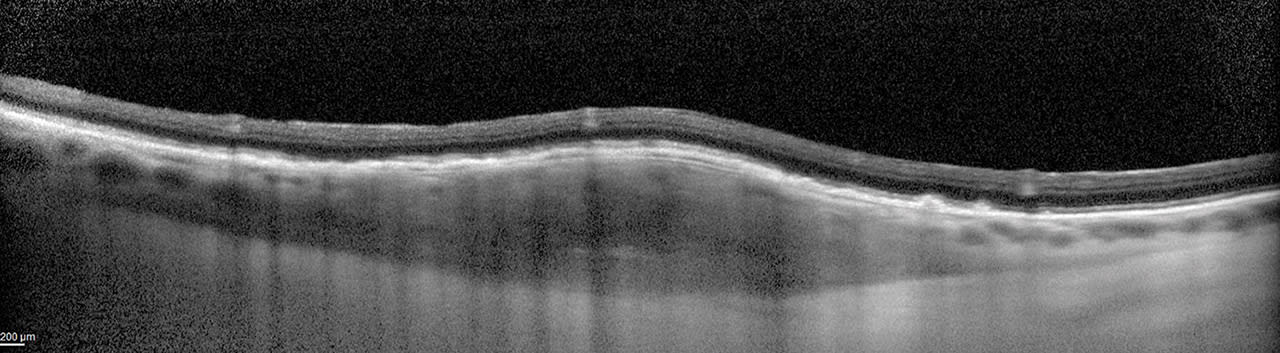

Central serous chorioretinopathy (CSCR) can present on standard OCT with subretinal fluid and no elevation of the retinal pigment epithelium (Figures 4 and 5). In these eyes, the choroidal thickness can be increased under the area of subretinal fluid. This finding can assist in differentiation from other pathology, such as choroidal neovascularization.1